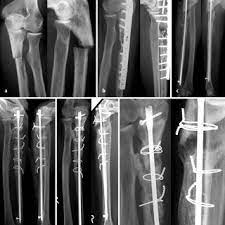

Intramedullare Nagelosteosynthese Der Ulna In Der Revisionschirurgie Springerlink

Pdf Intramedull Re Nagelosteosynthese Der Ulna In Der Revisionschirurgie